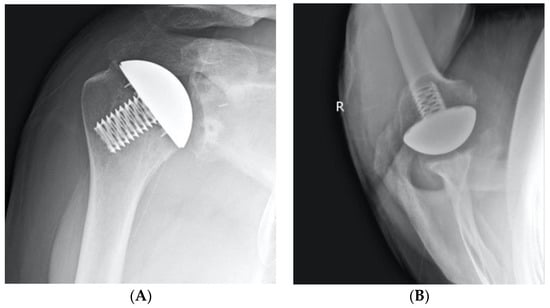

2.2. Surgical Technique